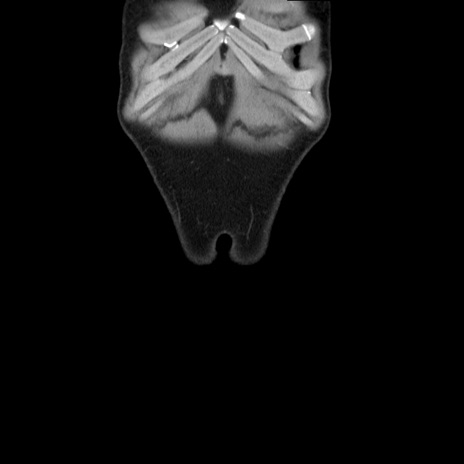

症例36(冠状断像)

【症例】20歳代 男性

【主訴】心窩部痛

【現病歴】今朝より上腹部痛あり。一旦軽快していたが再度出現したため救急要請。昨日夕に白身の魚を含む刺身を食べた。

【身体所見】BP 136/89mmHg、HR 74/min、BT 37.0℃、腹部:膨満、軟、心窩部に圧痛あり。反跳痛なし、筋性防御なし、腸雑音やや亢進あり。

【データ】WBC 17700、CRP 0.48